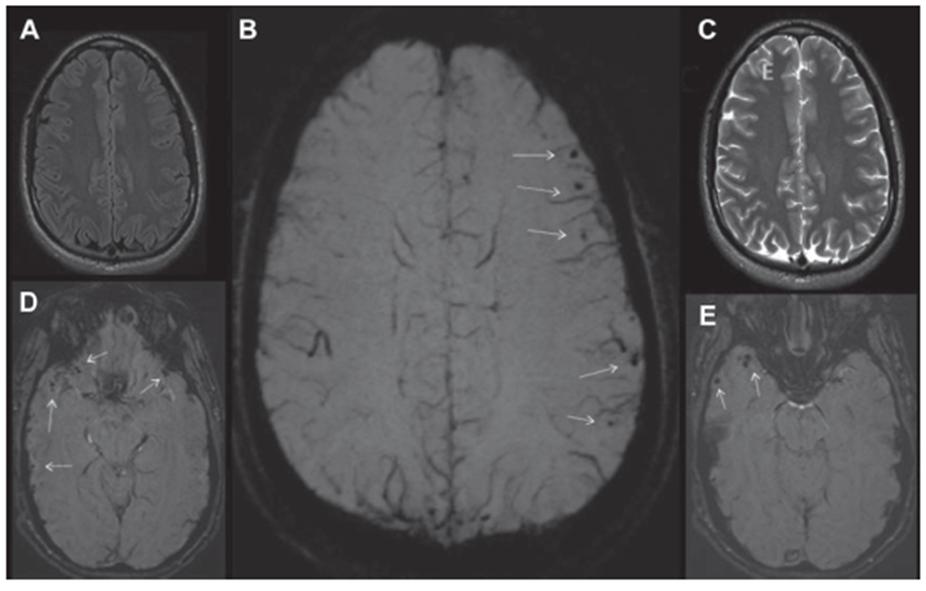

电离辐射治疗可导致直接和间接性脑损伤,包括CMBs、颅内海绵状血管畸形、脑白质病变和脑萎缩。

放疗相关CMBs和颅内海绵状血管畸形的确切机制尚不清楚。可能原因为放疗诱导的动态小血管样病变,其机制包括血管内皮生长因子表达增加、血脑屏障破坏、氧化应激和炎性改变。在既往接受了放疗的原发性中枢神经系统肿瘤生存者中,CMBs出现率高达2/3。

CMBs发生率和数量随着放疗时间延长而逐年增加,与放疗剂量和目标体积以及胚胎组织学呈正相关,与患者的年龄呈负相关。放疗后的CMBs以脑叶多见,且以枕叶为主。CMBs的出现与认知下降有关。

放疗 T2*WI示放疗前(A)、放疗后21个月(B)、放疗后33个月(C)、放疗后44个月(D)和放疗后62个月(E)。CMBs随时间的延长而增多。